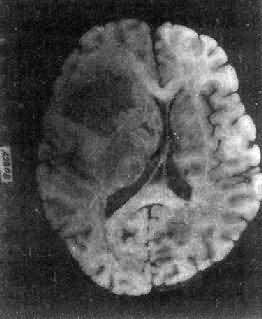

肉眼观,肿为数厘米的结节至巨大块状。分化较好的肿,境界不清;而分化程度较低的肿则境界分明。体灰白色。质地视肿内胶质纤维多少而异,或硬、或软、或呈胶冻状外观,并可形成大小不等的囊腔。由于肿的生长、占位和邻近脑细胞的肿胀,脑的原有结构因受挤压而扭曲变形(图16-23)。

图16-23 星形胶质细胞

左大脑半球肿胀,肿边界不清,部分呈胶冻状

高度恶性的星形胶质细胞称为多形性胶质母细胞(glioblastoma multiforme),多见于成人。肿好发于额叶、颞叶白质,浸润范围广,常可穿过胼胝体到对侧,呈蝴蝶状生长(图16-24)。体因常有出血坏死而呈红褐色。镜下,细胞密集,异型性明显,可见怪异的单核或多核巨细胞。出血坏死明显,是其区别于间变性星形胶质细胞的特征。毛细血管明显增生,内皮细胞增生、肿大,可导致管腔闭塞和血栓形成。肿发展迅速,预后极差,患者多在2年内死亡。

图16-24 多形性胶质母细胞

在两半球内肿呈蝴蝶状,边界不清,切面见有出血、坏死及液化